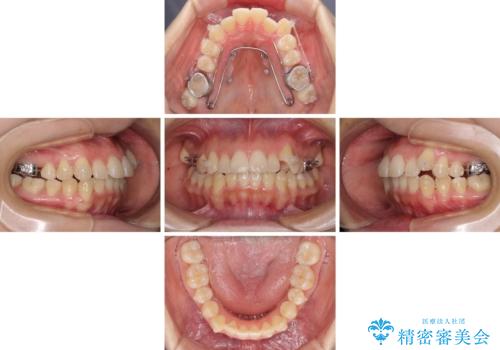

インビザラインによる矯正治療を希望されたため、上顎歯列の側方拡大奥歯の遠心移動のための補助装置を併用し、その後はインビザラインにて行うこととしました。

八重歯の動きが鈍く、治療期間は長期化しました。

癒着の疑いもありましたが、アンカースクリューを多用し、何とか改善することができました。